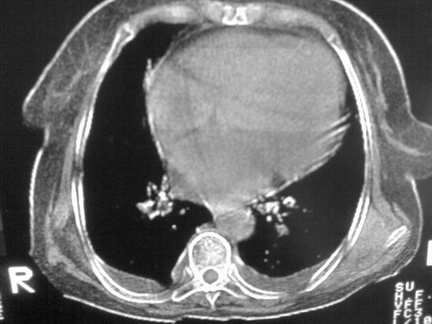

标题: CT13142:女 80 胸闷、气短、1w [打印本页]

标题: CT13142:女 80 胸闷、气短、1w

双侧胸腔积液

右肺感染;双侧胸腔少量积液,心影增大,可能与心功不全有关;胸内甲状腺肿。

胸内甲状腺肿;右肺中叶感染;双侧胸腔少量积液;心影增大,考虑有心功能不全。